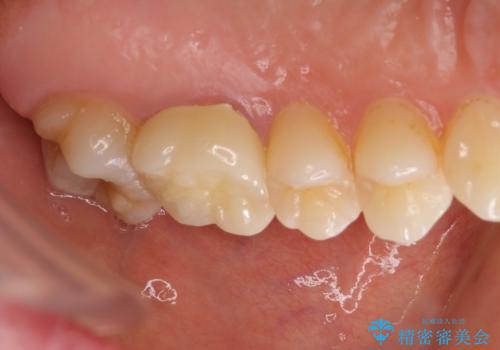

海外転勤が決まり、急いでセラミック治療をしてほしいとご来院された患者様です。

根管治療に症状がなく、上の歯に関しては土台もそのまま使用可能であったため、下の歯の土台、上下の歯のセラミック治療を行いました。